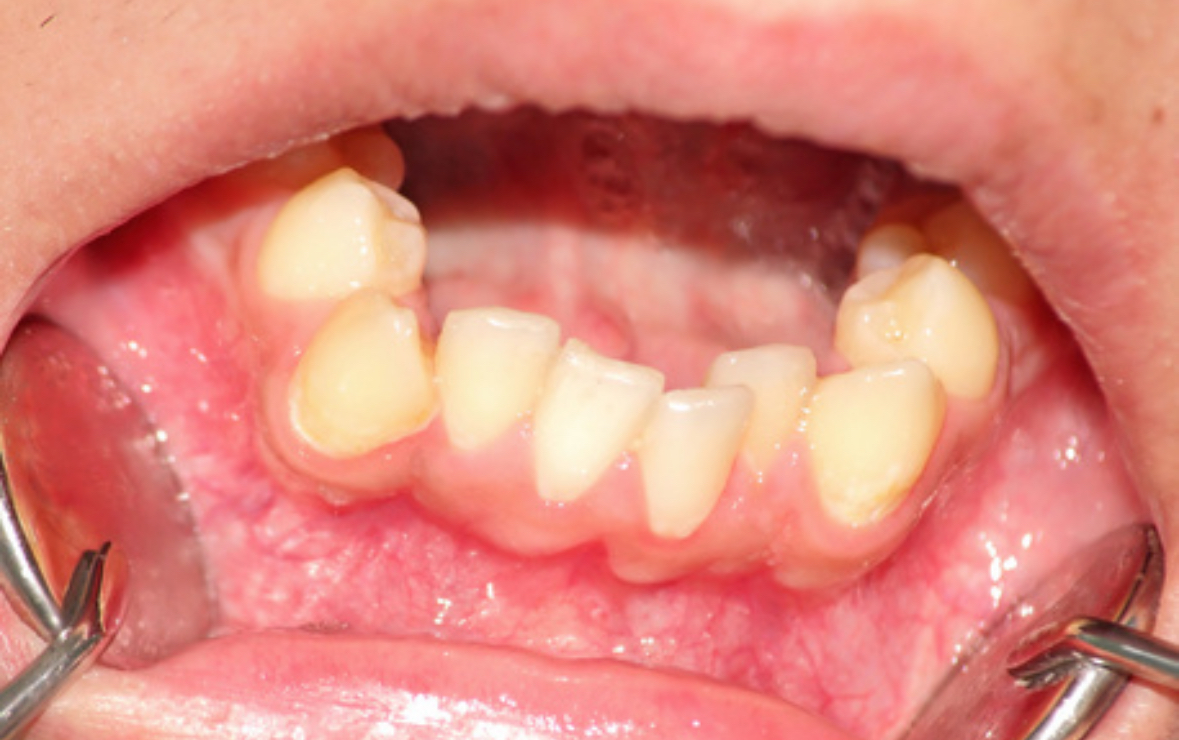

牙齒不齊不僅僅是美觀問題,它還可能對口腔健康產生深遠影響。從日常清潔難度增加到咬合功能受損,牙齒排列不良可能導致一系列口腔健康問題。珠海六和口腔醫院將深入探討牙齒不齊與口腔健康之間的關系,并提供維護口腔健康的建議。

牙齒擁擠或錯位使得牙刷和牙線難以到達所有角落,導致食物殘渣和細菌容易滯留,增加了患齲齒(蛀牙)和牙齦炎的風險。

不齊的牙齒會壓迫周圍的牙齦組織,造成牙齦紅腫、出血甚至退縮。長期下來,可能會發展為更嚴重的牙周病,威脅牙齒根基。